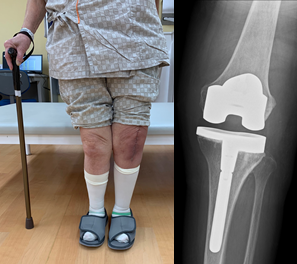

人工膝関節全置換術 (total knee arthroplasty: TKA)

- 末期の変形性膝関節症に対しては、TKAを行います。

患者さんの術前の膝関節可動域や画像所見を十分に検討し、それぞれに適したインプラントおよび術式を選択しています。また、手術精度の向上を目指したコンピュータナビゲーションを2機導入し、より正確な手術の達成や臨床研究のデータ解析に活用しています。 - さらにコンピュータ支援手術の開発を行なっています。

両側O脚変形、両側同時TKA